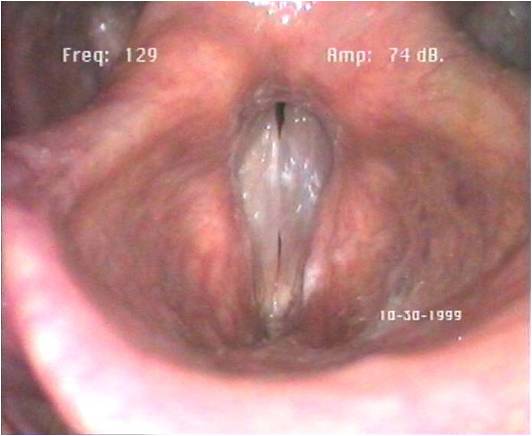

Voici deux images de larynx, 1 et 2 et deux sons de voix. A et B A quel larynx attribuez*vous chaque voix ?

Larynx1  Larynx2

Larynx2

A quelle personne, numérotée 1 ou 2 attribuez-vous une  paralysie récurrentielle ?